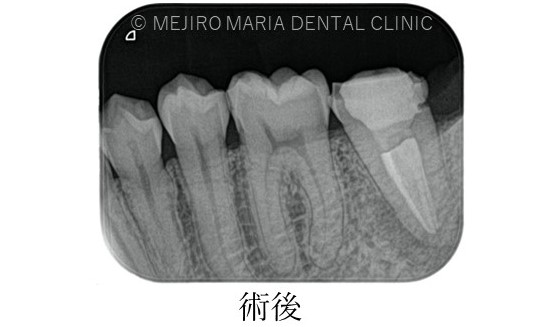

に対する、精密根管治療のアプローチ(再根管治療)_治療前後比較治療前のレントゲン画像.jpg)

に対する、精密根管治療のアプローチ(再根管治療)_治療前後比較治療後のレントゲン画像.jpg)

バイオセラミックにて根管充填を行いました。レントゲン写真からは根尖まで良好に隙間なく根管充填を行っていることが確認できます。

1回目の治療終了後、2週間後には違和感等は感じられないようにまで回復しました。